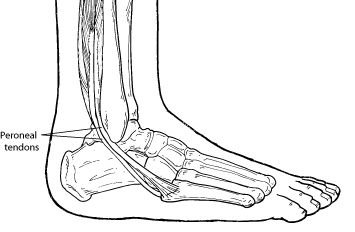

A tendon is a band of tissue that connects a muscle to a bone. The two peroneal tendons in the foot run side-by-side behind the outer ankle bone. One peroneal tendon attaches to the outer part of the midfoot, while the other tendon runs under the foot and attaches near the inside of the arch. The main function of the peroneal tendons is to stabilize the foot and ankle and protect them from sprains.

A tendon is a band of tissue that connects a muscle to a bone. The two peroneal tendons in the foot run side-by-side behind the outer ankle bone. One peroneal tendon attaches to the outer part of the midfoot, while the other tendon runs under the foot and attaches near the inside of the arch. The main function of the peroneal tendons is to stabilize the foot and ankle and protect them from sprains.